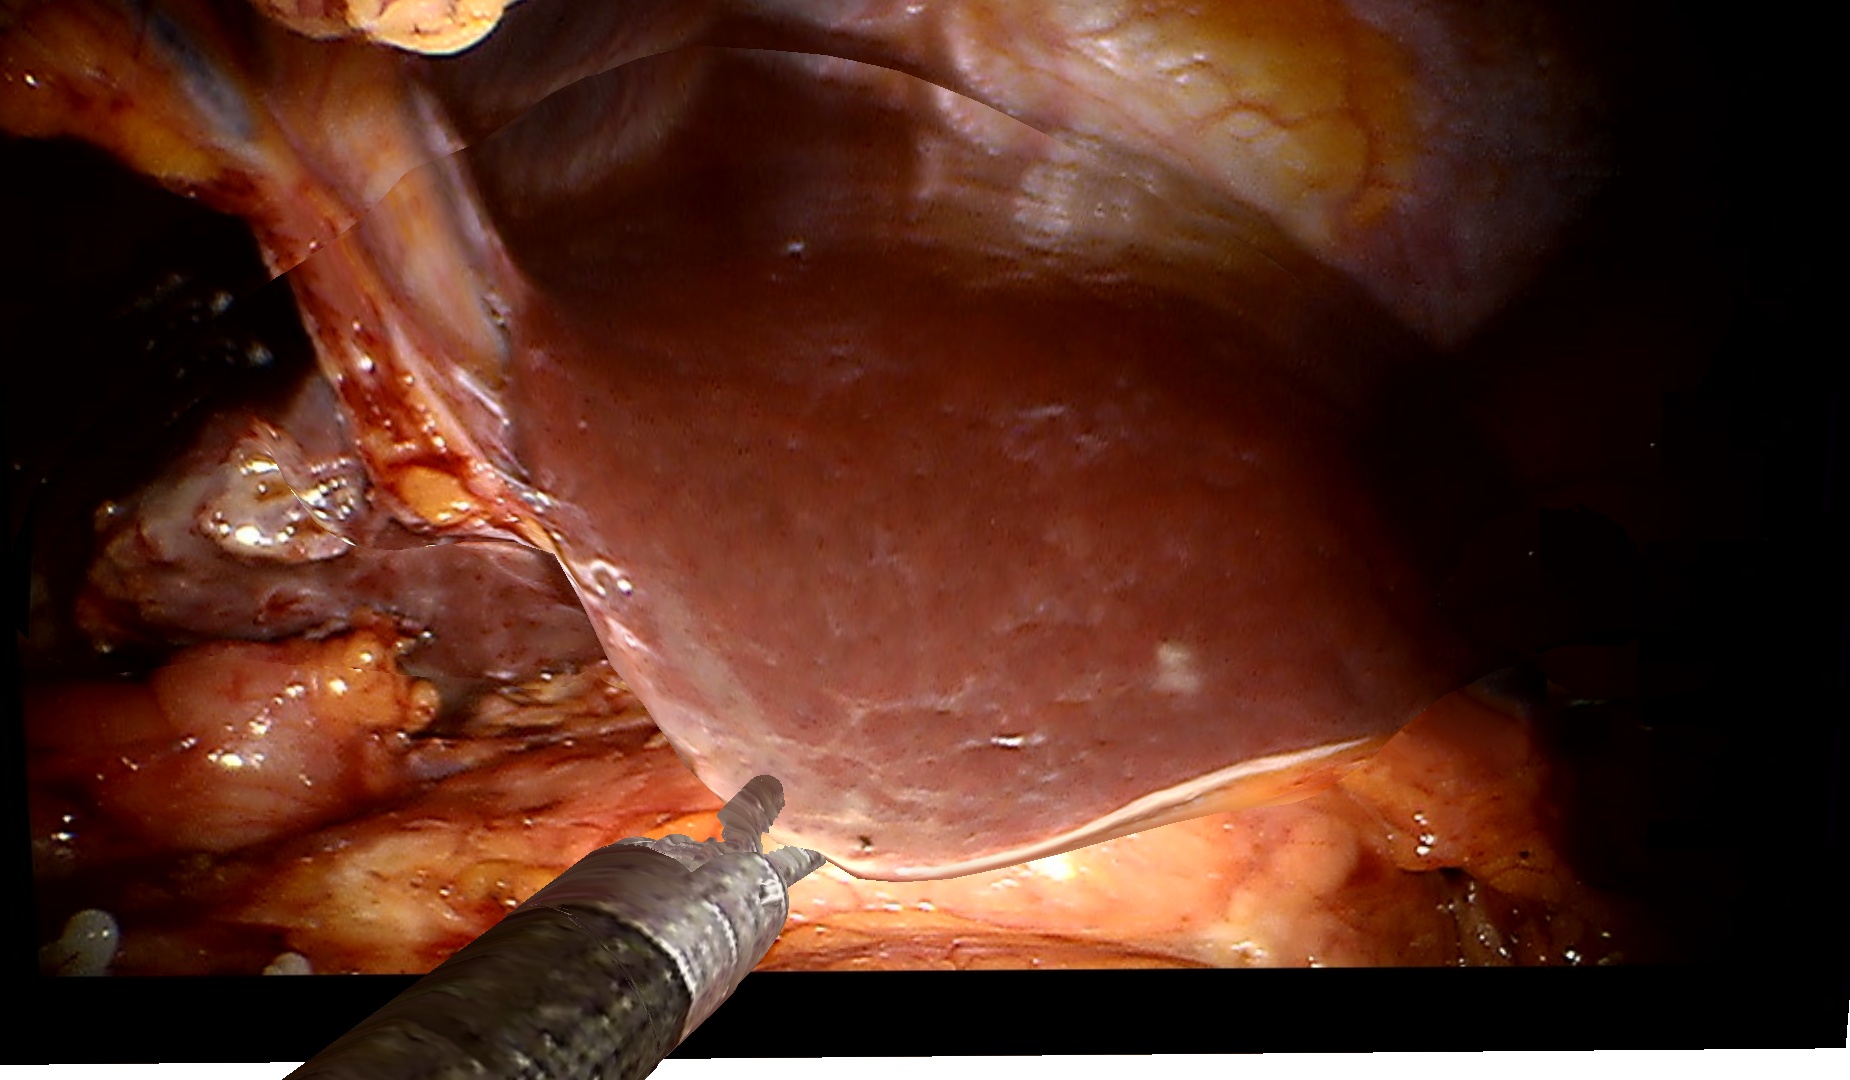

3.0.2 Qualitative Evaluation on Clinical Data

To demonstrate the effectiveness of our method on clinical data, we use a dataset of two visceral pig surgeries with a preoperative post-insufflation CT, initial rigid registration, a tracked laparoscope, and corresponding 2D monocular RGB videos. Surgical tools were masked out using SurgicalSAM [23]. The first sequence from the first surgery shows a tool-tissue interaction, whereas the second one shows a breathing motion without external manipulation. Because there is no deformed ground truth, as measuring intraoperative deformation would require intraoperative scanning, we demonstrate qualitative results.

Figure˜4 shows results on the tool-tissue interaction. The surgical tool presses down on the stomach, leading to the deformations tracked in the deformed mesh and CT (bottom rows). Although the difference in pressure applied between B and C appears marginal, we successfully track the increasing deformation, the difference being visible in both mesh and CT. For D and E, the tool is repositioned, now pulling the stomach back. Note how this backward pull is visible in the respective deformed CTs by a deformation to the right, since the laparoscope captures the scene roughly in the coronal plane, whereas the CT slice is shown in the sagittal plane.

Figure 4: Examples from a tool-tissue interaction sequence. Rows from top to bottom: input images acquired by the laparoscope, images rendered with our method, deforming mesh, and deforming CT. Arrows in A point to the deforming anatomical structure, circles in B highlight the area of deformation, and arrows in E visualize the pull direction. See video in the supplementary material.

Since we rely on an initial registration, we are also subject to registration errors. There is a slight misalignment between the structure being manipulated in the input images (stomach) and the deforming mesh. Also note that we initialize our mesh from a post-insufflation CT, ensuring that the initial mesh and the intraoperative state early in surgery are still very similar. Regarding the deformation of the CT, we can only capture surface deformations by deforming our mesh. A more realistic deformation of deeper layers would require biomechanical modeling. Apart from those caveats, the method does not work in real time yet. Given the strides being made in the 3D computer vision community around 4DGS, we are confident that this problem will be solved soon. Despite those limitations, the deformations of the stomach in the CT are sensible and correspond to the tool-tissue interaction as confirmed by a board-certified surgeon.